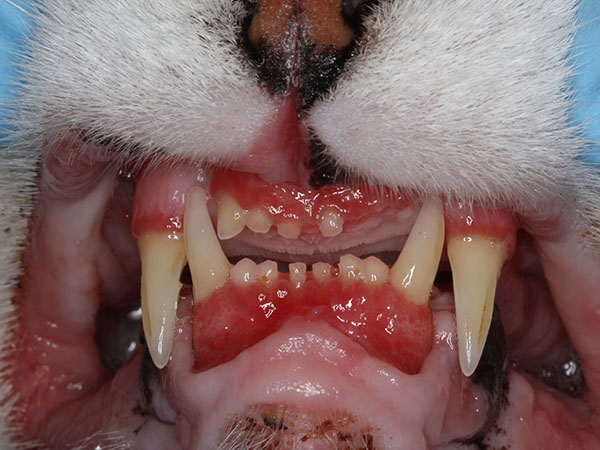

Stomatitis is a generalized term that refers to inflammation of the mouth. However, this painful condition is caused by specific diseases that affect both cats and dogs, and it can be devastating to you and your pet. The term stomatitis in cats refers to feline chronic gingivostomatitis. In dogs, the disease is commonly called canine plaque-reactive stomatitis, or chronic ulcerative paradental stomatitis (CUPS). In both cases, there is an underlying immune-related disorder that results in inflamed and painful surfaces of the cheeks, tongue, and gums.

FCGS is an autoimmune condition in which the cat’s immune response to the teeth and/or oral bacteria is abnormally strong. This results in inflammation and pain that can range from mild to severe. The inflammation centers on the back of the mouth, as well as around the teeth, lips and tongue. While there may be an underlying viral trigger, the exact cause is still unknown. Rarely, FCGS can be managed by maintaining a very clean mouth (anesthetized cleanings at regular intervals and daily brushing at home). Oftentimes, however, more aggressive intervention is needed to help your cat stay comfortable.